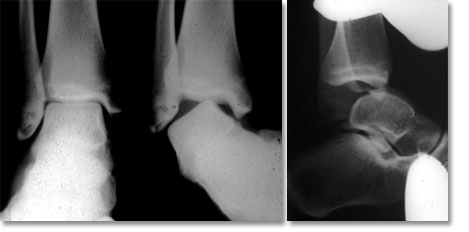

Le Diko - laxité